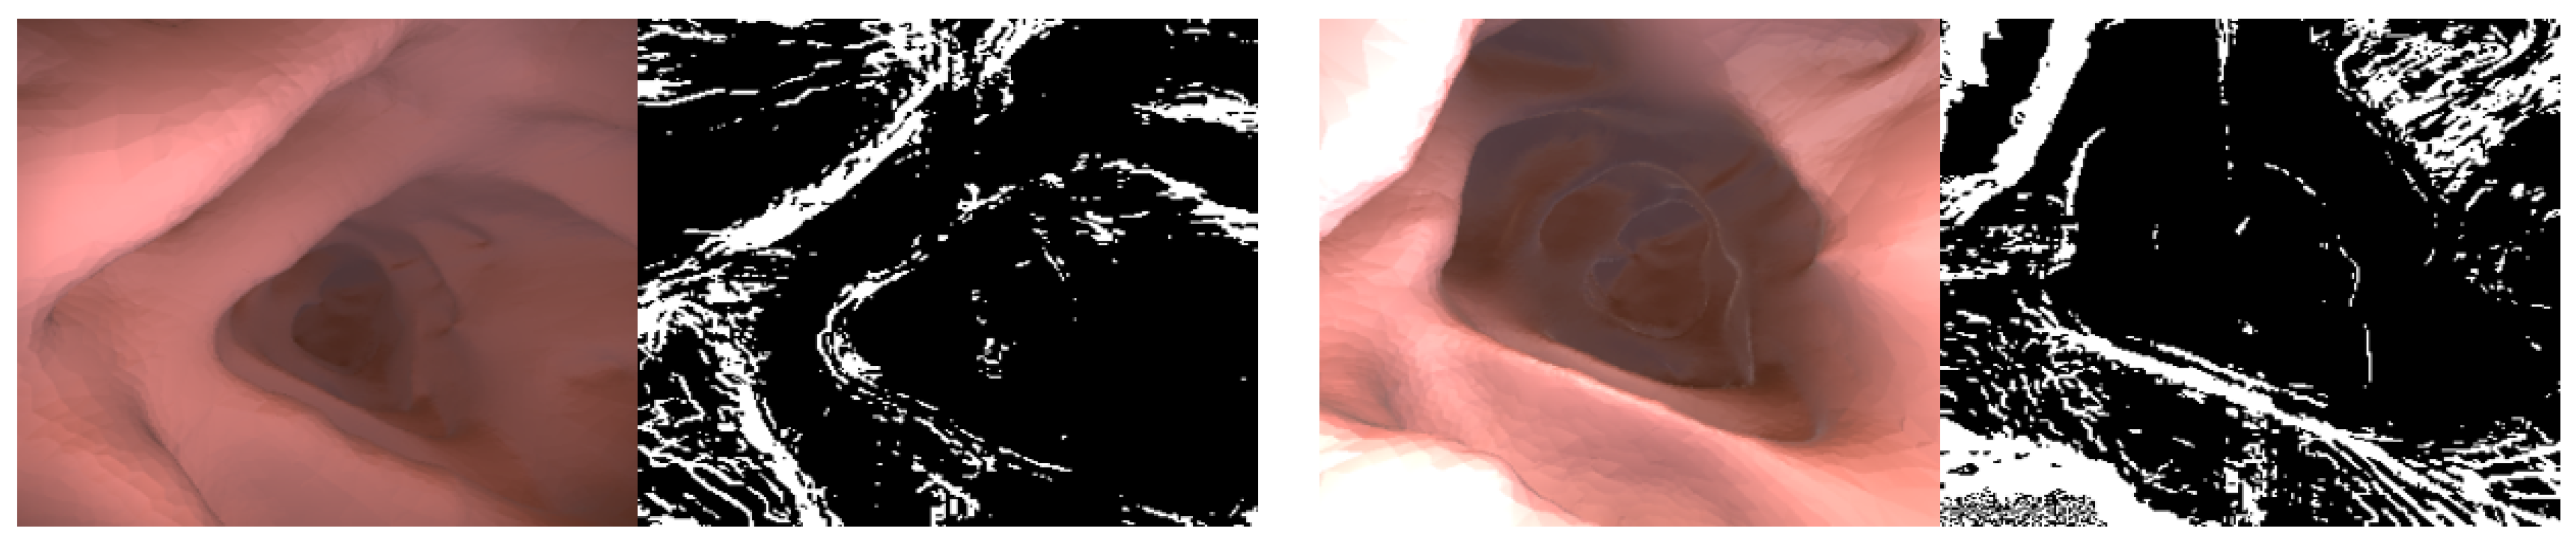

3.2. Improved Self-Supervised Training

3.2.1. Depth Reconstruction Loss